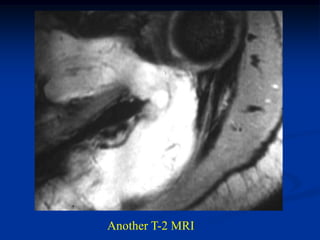

Another T-2 MRI

Axial T-2 MRI